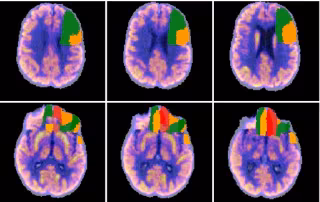

La compañía biotecnológica gallega Qubiotech Health Intelligence, dedicada al desarrollo y comercialización de software para mejorar el diagnóstico y seguimiento de enfermedades neurodegenerativas, ha cerrado una ronda de financiación para consolidar su crecimiento y preparar su internacionalización.

La compañía, que utiliza el procesamiento de imágenes basado en Inteligencia Artificial para el desarrollo de diagnósticos, ha anunciado que de esta manera han entrado en su accionariado los fondos especializados Sémola Tech Ventures y Nowture.